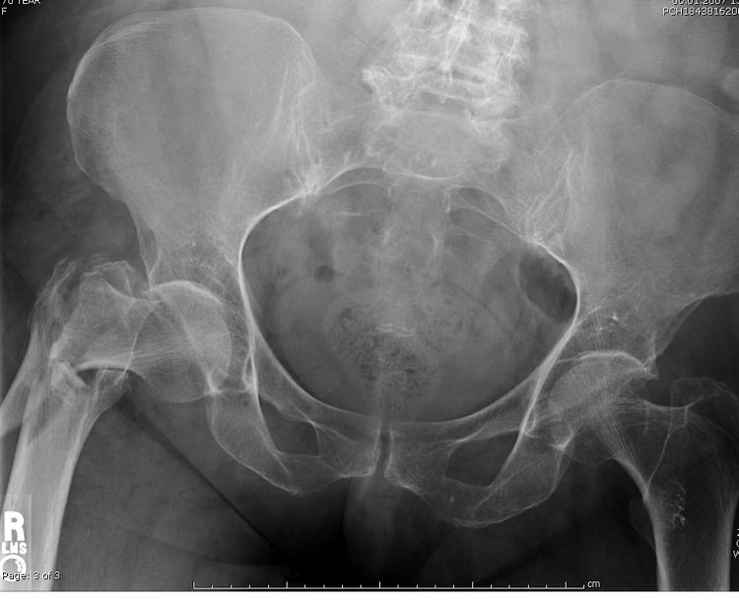

Здесь 83 года, травма в результате падения

Djoldas Kuldjanov, M.D.

Department of Orthopedic Surgery

St. Louis University